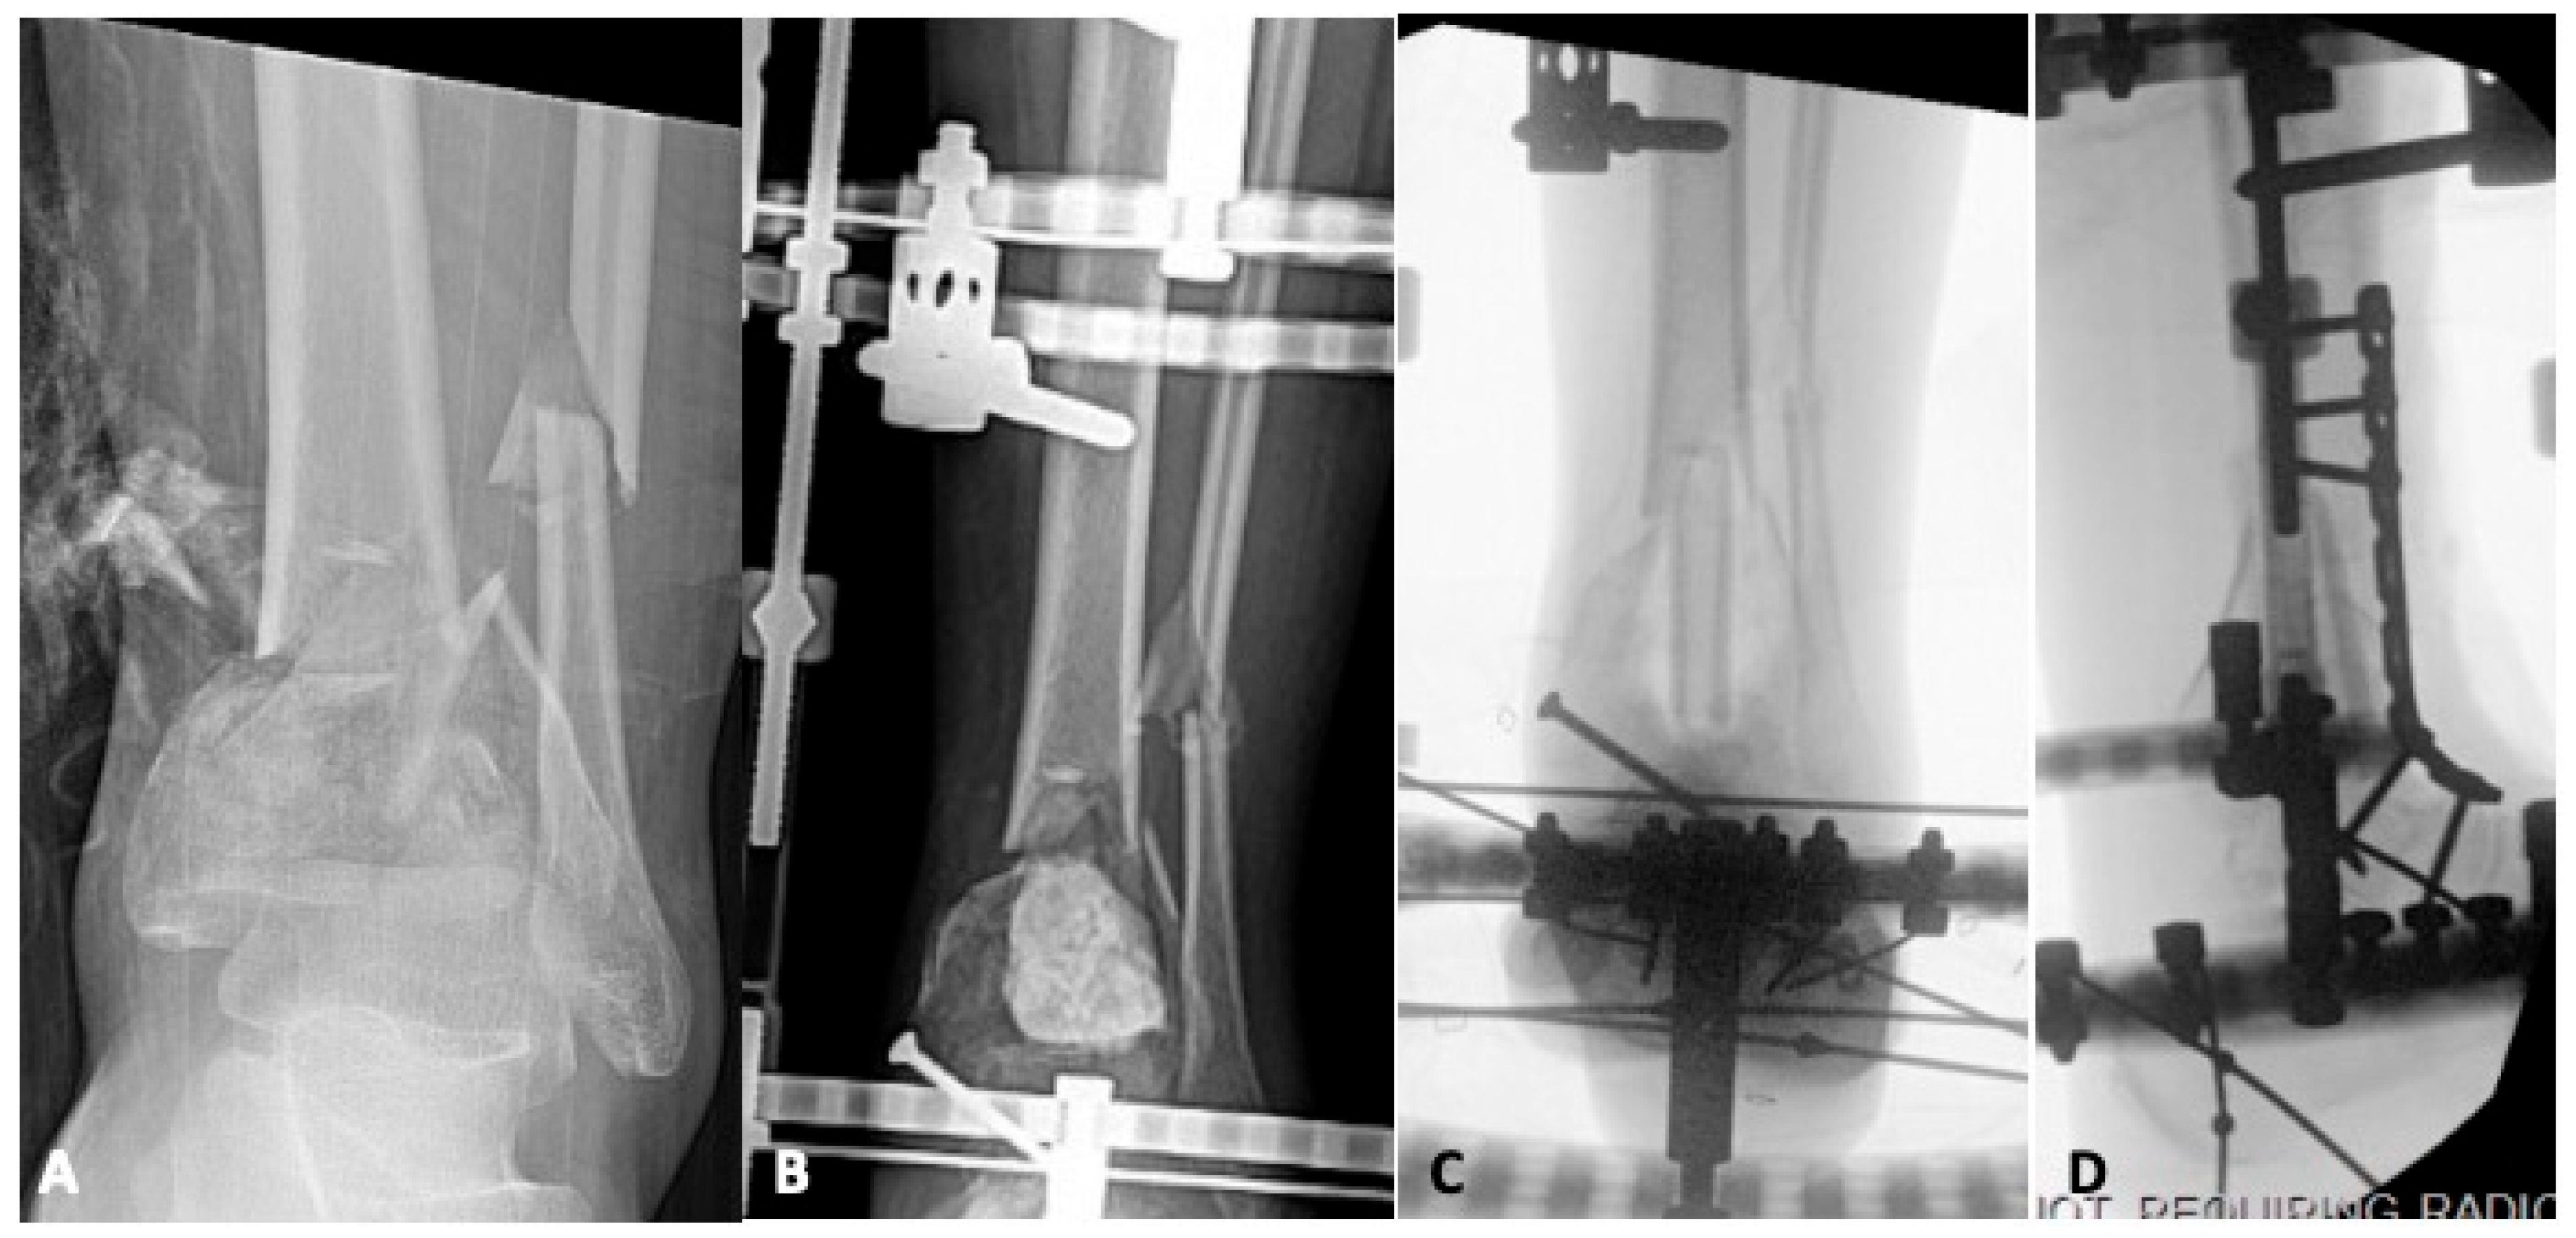

4.1. Infection

5.1. Revision Operative Fixation

5.2.2. Tibiotalar Arthrodesis